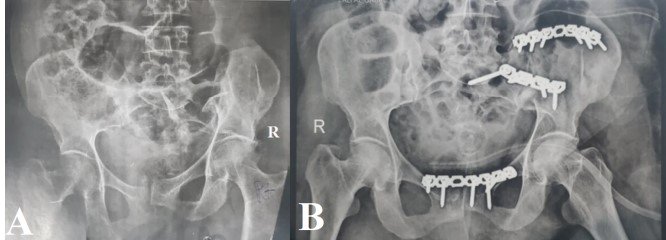

Methods: This prospective cohort study was conducted at the Military General Hospital and Al-Thawra Modern General Hospital in Sana’a, Yemen, between April 2019 and April 2023. We enrolled 76 patients aged 16– 60 years with unstable pelvic ring fractures that required surgical intervention (Tile type B/C). Data on patient demographics, mechanism of injury, fracture classification (Tile and Young-Burgess), surgical approach, and complications were collected and analyzed. Anatomical reduction was assessed using the Matta and Tornetta criteria, respectively. Functional outcomes were evaluated using the Majeed scoring system at a mean follow-up of four years.

Results: The mean patient age was 34 years, and the majority of patients were male (68.4%). The most frequent mechanisms of injury were motorcycle accidents (30.3%) and car accidents (27.6%), followed by falls from a height (26.3%). According to the Tile classification, the most frequent fracture patterns were C2 (36.8%) and C1 (34.2%). Postoperative radiological assessment revealed excellent reduction in 69.7% of patients. The overall complication rate was 30.3%, with wound infections (9.2%) being the most common. According to the Majeed Functional Outcome Score, 63.2% of the patients achieved excellent results. Statistical analysis revealed a significant positive correlation between the quality of radiological reduction and final functional outcomes (p < 0.05).